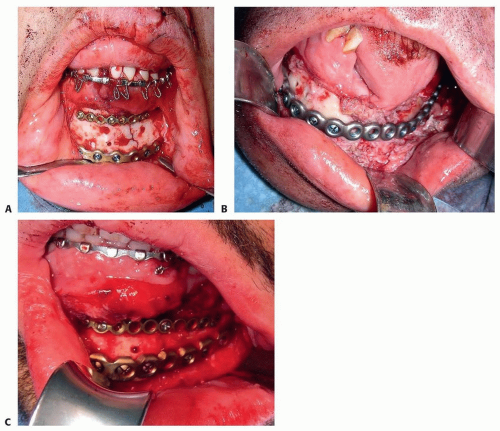

One of the more common techniques for addressing midfacial fractures, often referred to as “outside-in” technique, focuses on first repairing the zygomatic arch to correct facial width.

The “bottom-to-top” approach focuses on reconstruction of the mandible first—generally accomplished as the

mandibular bone is less prone to comminution in most causes of panfacial trauma—which results in larger bone fragments that are technically easier to repair.

FIG 2 • The “outside-in” technique focuses on repairing the zygomatic arch first in order to correct facial width.

The “top-to-bottom” approach initiates repair at the forehead before working down to the maxilla and mandible (FIG 2).

The “bottom-to-top-to-middle” approach focuses on reconstruction of the mandible first—generally accomplished first because the mandibular bone is less prone to comminution in most etiologies of panfacial trauma—which results in larger bone fragments that are technically easier to repair.

Attention is then directed toward the zygomatic arches/frontal bar regions and the NOE/orbit, correcting any discrepancy at the Le Fort I level as the final intervention.

Possible incisions for gaining access to the mandible include the following:

Anterior degloving (FIG 3A)

Intraoral degloving (FIG 3B)

Posterior degloving (FIG 3C)